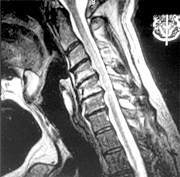

Figure 2: MRI study obtained after the chair incident. A marked progression of disc herniation and Modic type I changes are present, indicating a new level of inflammatory change associated with the recent trauma.

This 50-year-old male patient had a long history of neck pain and had been treated successfully in the recent past with a series of epidural steroid injections. While he was sitting in a standard office swivel chair, the base of the chair broke and he fell backward, landing on the floor. His point of contact with the floor was his upper back. His neck pain complaints and radiculopathic symptoms returned following this fall. A second course of epidural steroid injections was unsuccessful, as were all other conservative measures, and he eventually had a bi-level cervical discectomy and fusion with anterior plating. An MRI study obtained after the fall was compared to an MRI study taken a year prior to the fall and demonstrated a significant progression of the herniations at two levels and a significant progression of type I bone marrow changes in adjacent vertebral bodies (Figures 1 and 2).

The defense team argued the current complaints were similar to the complaints he'd had in the past and that, based on his previous MRI findings, this represented only a natural progression of his pre-existing condition, not a traumatic aggravation. Using measuring tools, I was able to demonstrate a three-level herniation progression of 47.5 percent, 27 percent, and 41.5 percent at the C4-5, C5-5 and C6-7 levels, respectively, over such a short period of time as would have been very unlikely absent an intervening trauma. We also were able to show the increase in the adjacent Modic changes provided additional objective evidence of a new inflammatory aggravation. At the settlement conference hearing, the defense tendered a very favorable offer.